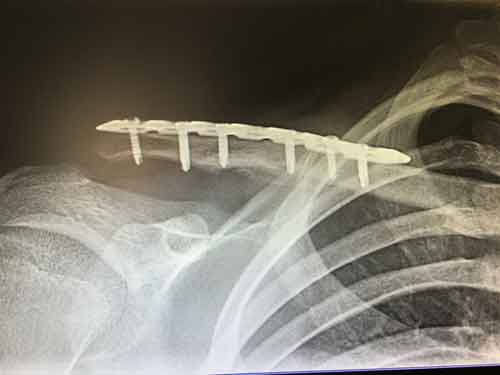

Die sogenannten Marknägel sind Implantate aus Titan oder Edelstahl. Damit werden die gebrochenen Knochenfragmente miteinander verbunden, was einer inneren Schienung gleichkommt.

Der große Vorteil der Verschraubung liegt in der rascheren Genesung. Bereits am Tag nach der Operation kann die Patientin oder der Patient unter physiotherapeutischer Anleitung erste Schritte machen. Der Gips oder eine äußere Schiene bleiben erspart. Im Regelfall haben Patienten nach einer Verschraubung sehr geringe Beschwerden.

Die Schrauben müssen auch nach kompletter Verheilung nicht entfernt werden. Es muss allerdings bei Flugreisen ein Implantatpass mitgeführt werden, da medizinische Schrauben die sensiblen Metalldetektoren bei den Sicherheitskontrollen auslösen können.